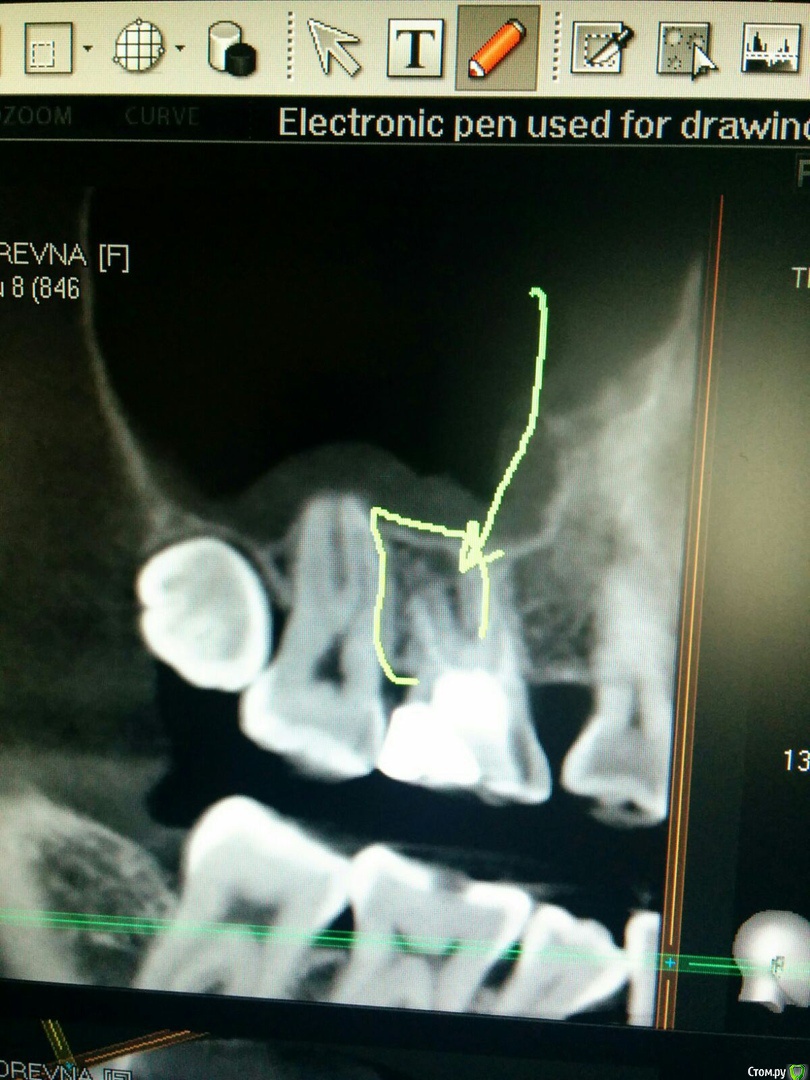

Ксения33 Опубликовано 30 сентября, 2020 Поделиться Опубликовано 30 сентября, 2020 (изменено) Уважаемые доктора, подскажите, пожалуйста, за какой срок восстанавливаются ткани периодонта? Мне перелечивали сложный зуб с хроническим периодонтитом. На снимках были значительные изменения. Как вы считаете, когда целесообразно сделать повторное КТ для оценки состояния периодонта в области этого зуба? Прикладываю снимки до перелечивания каналов. Изменено 30 сентября, 2020 пользователем Ксения33 Ссылка на комментарий